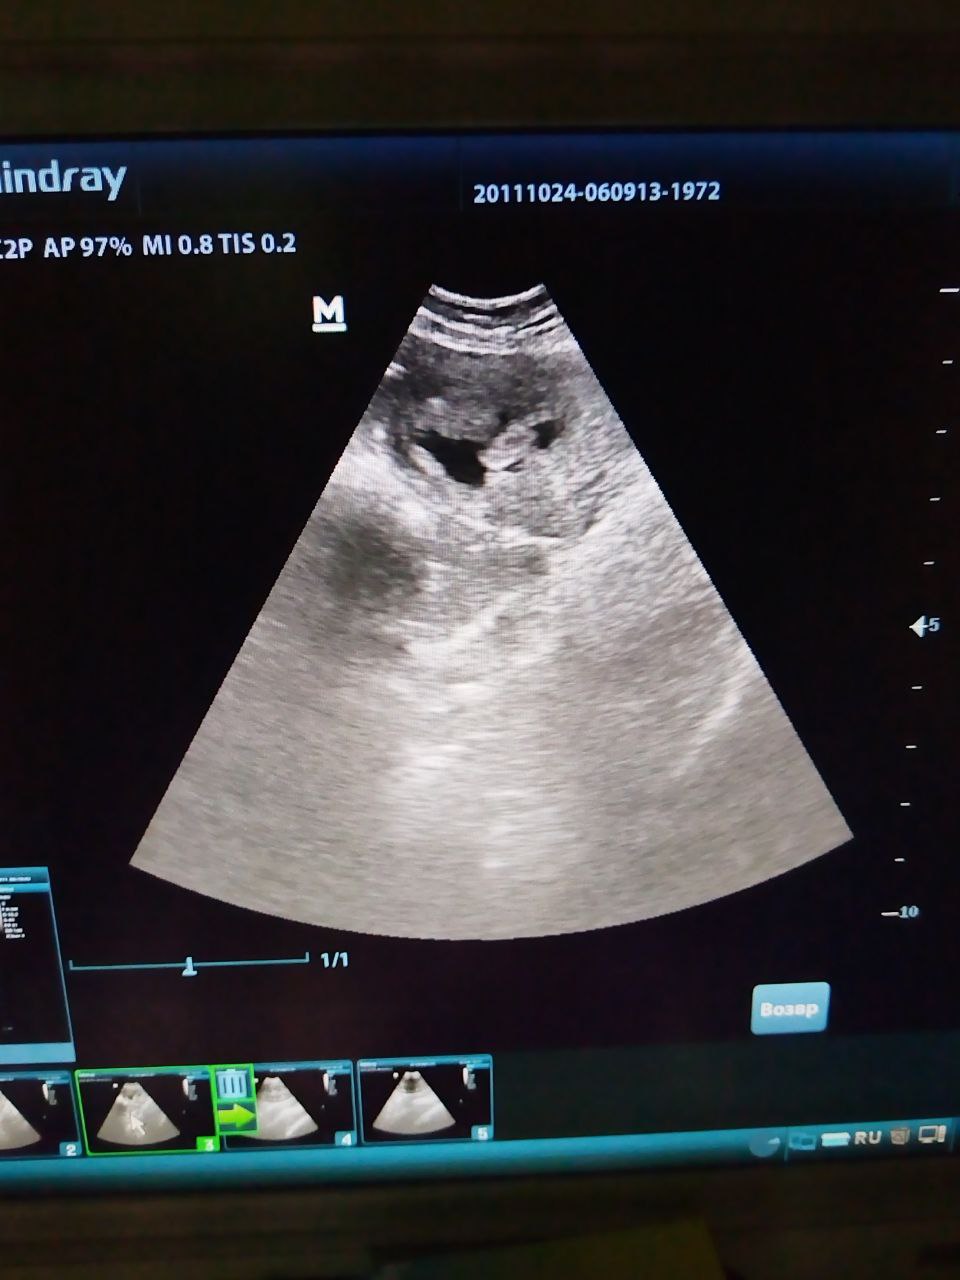

Владельцы собаки по кличке Гоша, возраст 9 лет, обратились в участковую ветеринарную лечебницу ОГУ «Саратовская межрайСББЖ» с жалобами на апатию, задержку мочеиспускания у своего питомца. Во время ультразвуковой диагностики ветеринарные специалисты обнаружили у животного отслойку стенки мочевого пузыря. Было назначено симптоматическое лечение (антибиотикотерапия, спазмалитики, кровоостанавливающие и обезболивающие препараты) и плановое УЗИ в динамике через 10-14 дней после проведенного лечения.